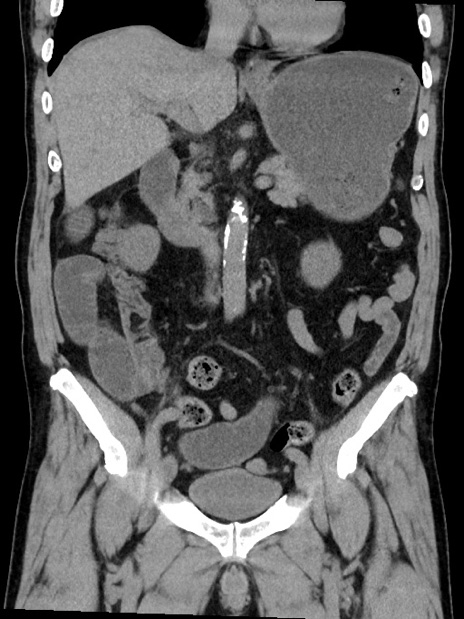

横断像

【症例】70歳代 男性

【主訴】腹部膨満、嘔吐

【現病歴】昨日より腹部膨満感出現。本日増悪し、仙痛出現。嘔吐あり、受診。

【既往歴】糖尿病、胆摘後

【身体所見】BP 149/80mmHg、HR 74/min、BT 35.9℃、腹部:膨満、軟、圧痛なし。腸雑音減弱あり。上腹部正中切開瘢痕あり。

【データ】WBC 13500、CRP 1.72